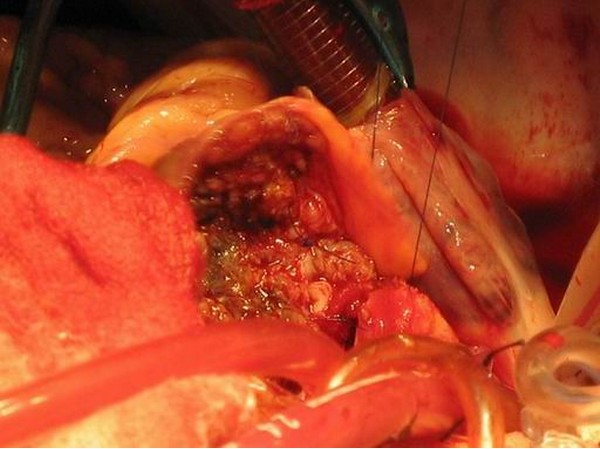

2003年12月29日于全麻、体外循环下行肿瘤切除术,术中见肿瘤位于主动脉根部前壁,与主肺动脉根部、右室流出道粘连紧密,3ⅹ4cm大小。右冠状动脉细小。沿肿瘤包膜外切除肿瘤,行右冠状动脉近段结扎,将右冠状动脉肿瘤供血部分切除,未行搭桥手术。以人工血管内衬自体心包修补主动脉,自体心包片修补主肺动脉前壁。手术后进ICU病房监护,24小时脱离呼吸机。

肿物病理回报:嗜铬细胞瘤。免疫组化支持该诊断。

两例患者的异位嗜铬细胞瘤除了上述特点以外还有自己的特点,1) 它生长的部位为主动脉根部或心脏表面,由冠状动脉供血或累及冠状动脉;2)肿瘤的部位紧邻主动脉根部、冠状动脉和主肺动脉,使肿瘤的切除变得十分困难;3)肿瘤的高分泌症状(高血压、心悸、多汗、头疼)明显,特别是血压和心率的波动更容易受到影响。

手术成功治疗切除异位嗜铬细胞瘤。